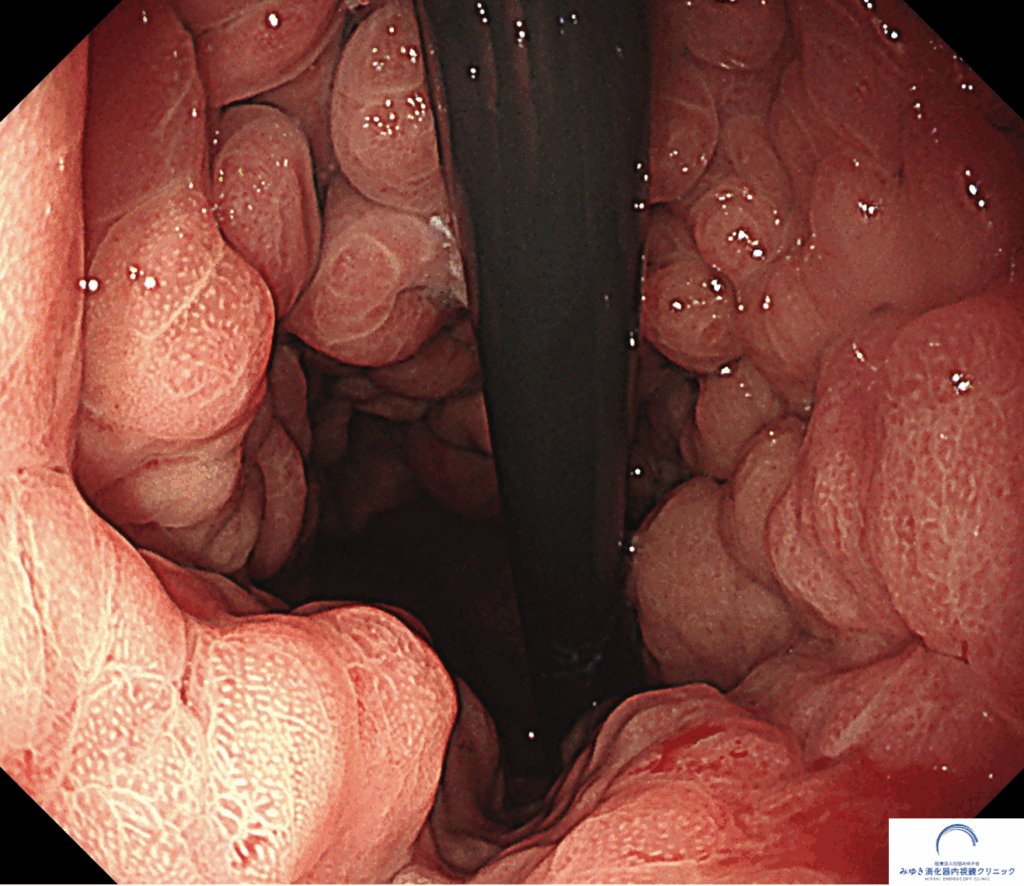

*参考までに正常な胃の写真です。ひだの太さと胃の広がり方が違うのが一目瞭然です。